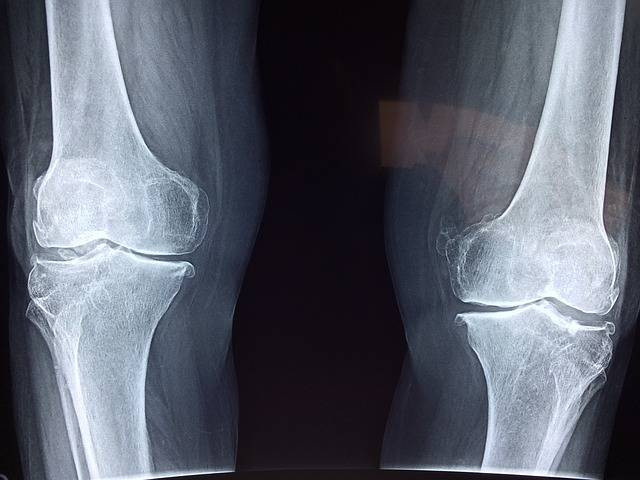

Sendi lutut